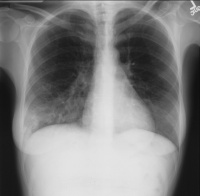

肺炎[编辑 | 编辑源代码]

肺炎是肺实质和间质,由于多种病原体引起其他如放射、化学、免疫、过敏及药物等因素亦能引起肺炎。